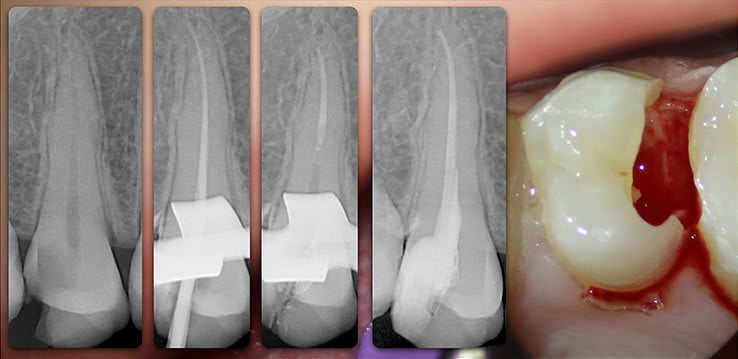

Template for x-rays